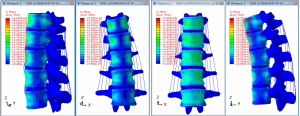

The stress clouds for vertical load, forward flexion, posterior flexion, and lateral flexion of the normal vertebral body are shown in Figure 13.

The images show that the anterior two-thirds of the vertebral body, the posterior part of the vertebral endplate, and the site near the pedicle were the areas with concentrated stress on the normal vertebral body in the vertical state, and the stress was distributed posteriorly and laterally. It was obvious that the stress on the cortical bone, especially the anterior edge of the vertebral body, was higher than that on the cancellous bone. When the vertebral body performed flexion or extension movement anteriorly, posteriorly, or laterally, concentrated stress occurred on both the flexion and extension sides and near the pedicle.

In the models with an implanted screw-rod system, the stress conditions of the five types of superior endplate collapse (defect volumes of 1/5, 2/5, 3/5, 4/5, and 5/5 of 2/3 of the anterior edge of the vertebral body, respectively) under vertical load, anteroposterior flexion, lateral flexion, and left-right rotation conditions were simulated. The stress distribution diagrams are shown in Table 3.